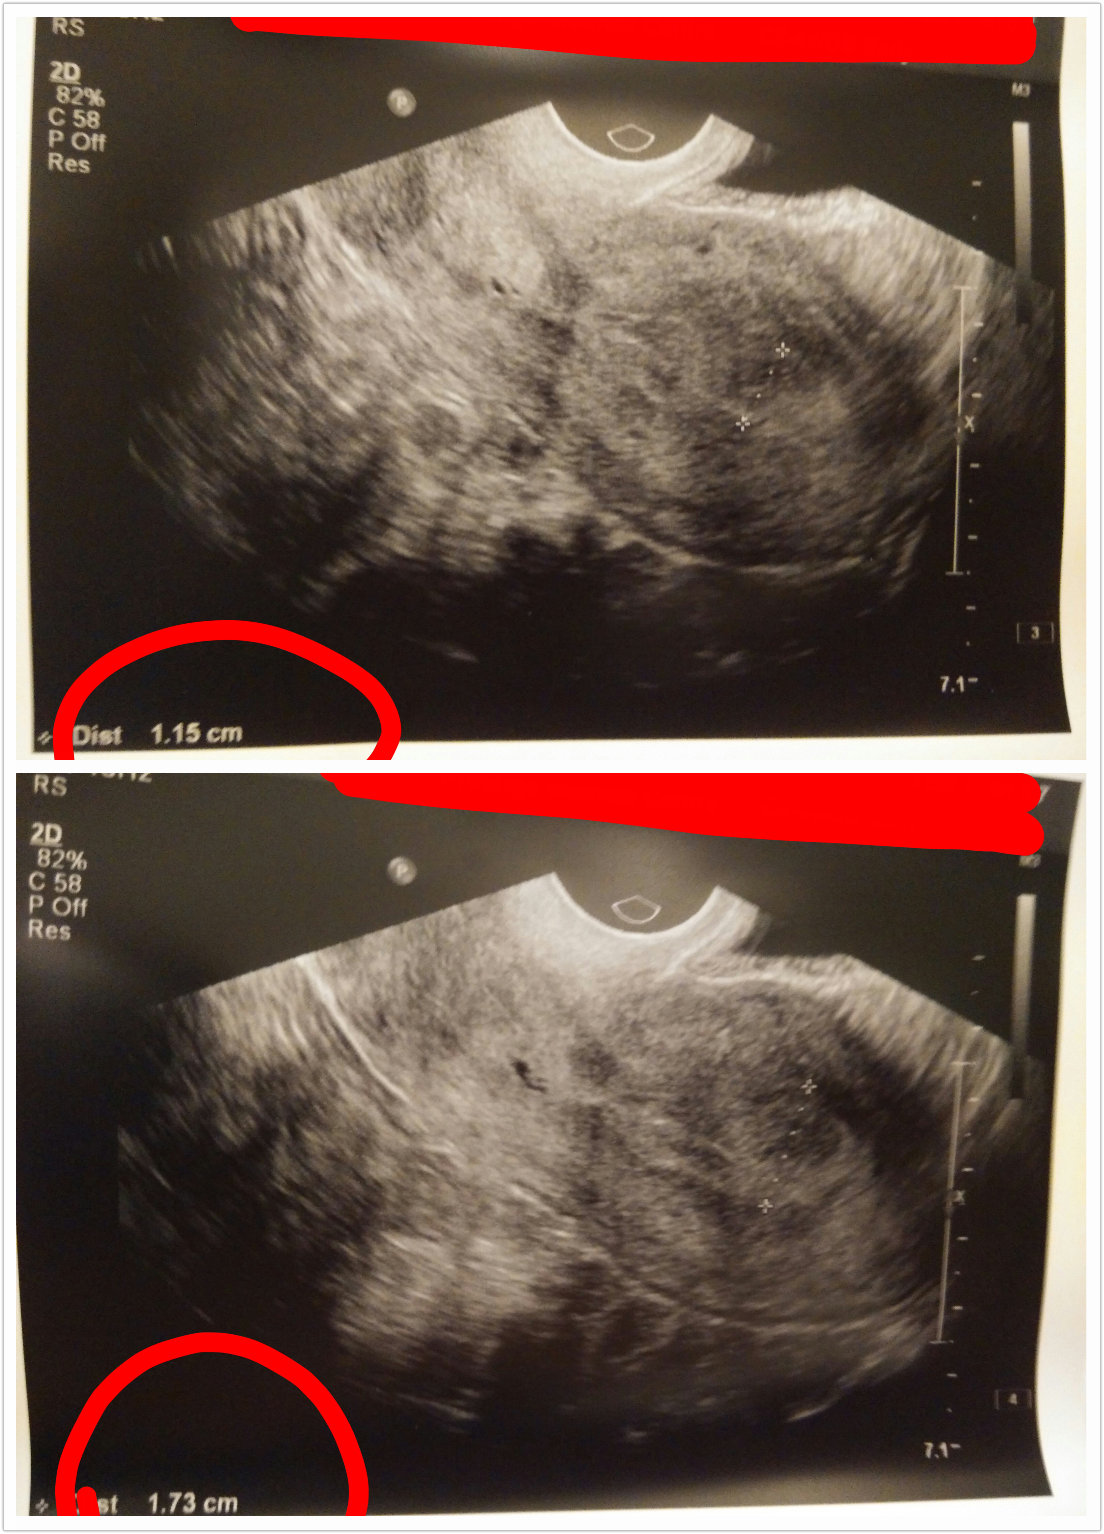

上星期五(17/7),我懷著緊張的心情去做檢查。

檢查目的有二,

一就是檢驗內膜厚度,二就是抽血驗黃體酮及雌二醇。

內膜厚度要在8mm至12mm之間才可以成行,

我一向的內膜也比較薄,所以對此項真是很擔心,

醫生先為我在肚皮上照超聲波,他說內膜有6mm,

果然真的不夠厚,但他說不準確的,

要照陰超才準確。

再超陰超,他說很不錯,有11.5mm,

最厚的地方還有17.3mm,他表示可以放胎,

此時我也很混亂,聽到他說不錯,即時心花怒放。

在抽過血,定過神後,再回顧剛才的照片,

才發現有問題,就是內膜最厚的厚度是17.3mm,

那不是代表超出了能放胎的範圍嗎?